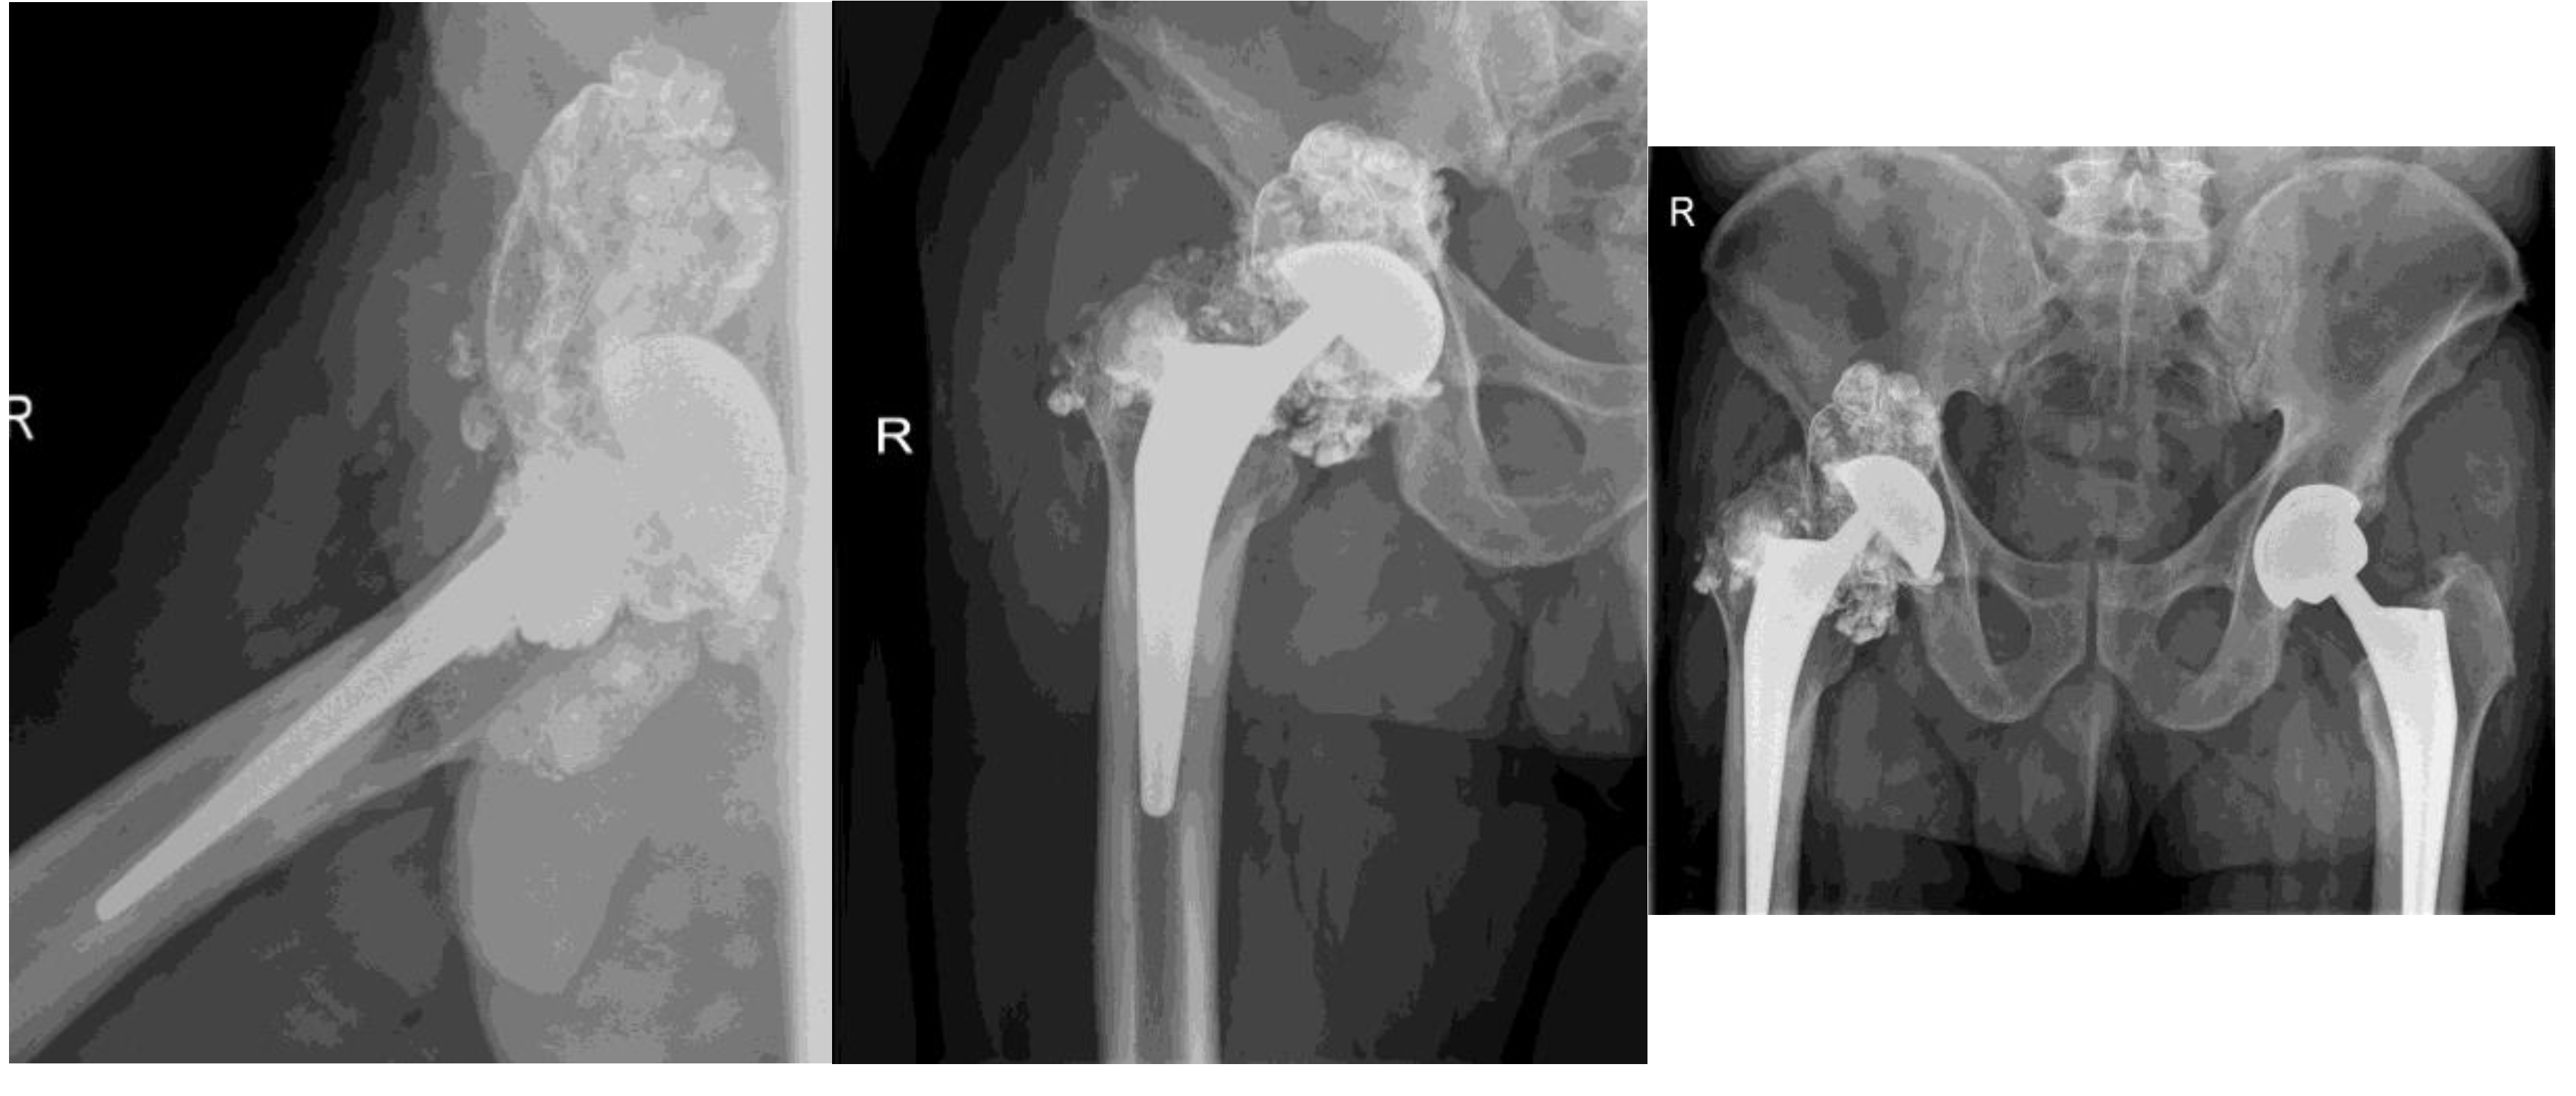

A 31. 3. 2021. Xray after revision surgery. Extensive metallosis was found and mosty removed. Damaged femoral head, polyethylene and acetabular cup were exchanged.

Proper symetrical positioning of components- after femoral head and acetabular componets were exchanged. A lot of metall infused soft tissues were removed- note diminished cloud around the prothesis.

B Routine x-ray at follows up 2 months after surgery- no dynamics

The patient was satisfied with the surgical outcome and reported only slight limitations in range of motion (ROM). He works as a painter (residential and commercial), and occasionally experiences pain following heavy work or lifting heavy objects. No other complaints were reported.

Figure 5. X-ray after revision surgery. Extensive metallosis was found and mosty removed. Damaged femoral head, polyethylene liner and acetabular cup were exchanged.